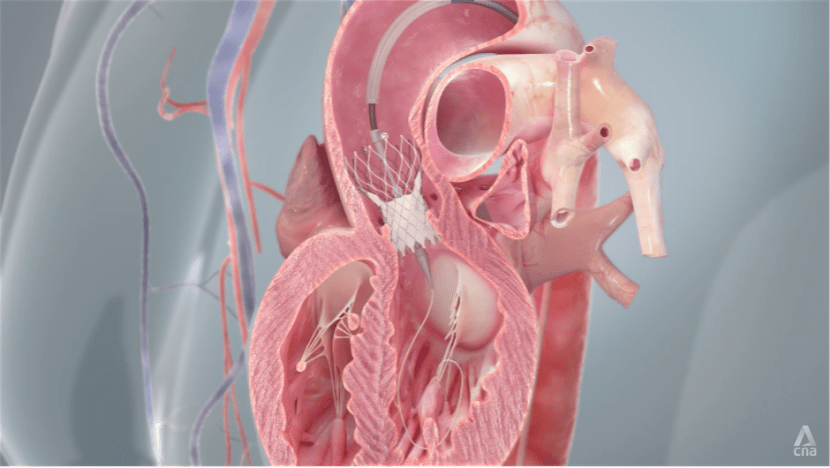

Over the last 20 years of medical advancement, minimally invasive procedures, such as the transcatheter aortic valve implantation (TAVI), have allowed patients to be treated without opening the chest.

TAVI is a minimally invasive procedure during which a new valve is inserted through a small incision in the thigh area while the patient is under sedation or local anaesthesia. Patients are usually hospitalised for three to four days and are able to go back to their usual activities quite quickly.

“The idea is to give patients efficient treatment whereby their symptoms are removed and allow them to do what they love,” says Dr Tay.